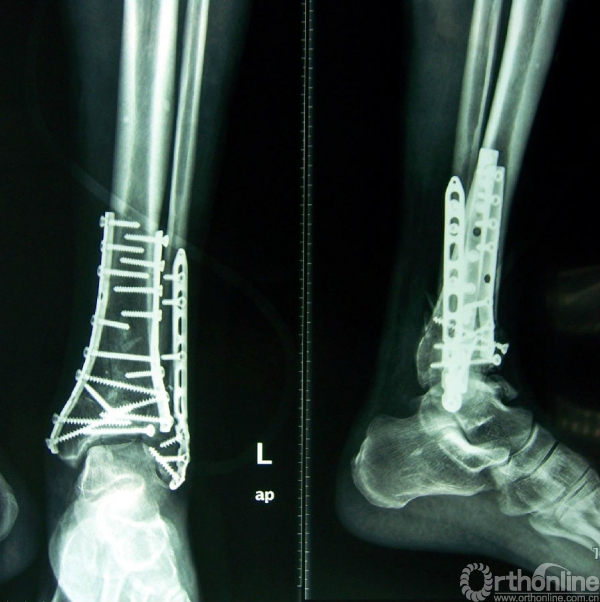

图4 男,41岁,左侧双柱pilon骨折。

4a.术前正位、侧位X线示胫骨远端粉碎性骨折,属于外侧柱的腓骨完整;

4b.CT水平面扫面及表面重建示内侧柱及中柱有明显的骨折;

4c.手术入路及1/3半管型钢板分柱固定情况;

4d.术后X线正侧位片示双柱pilon骨折对位、对线良好。